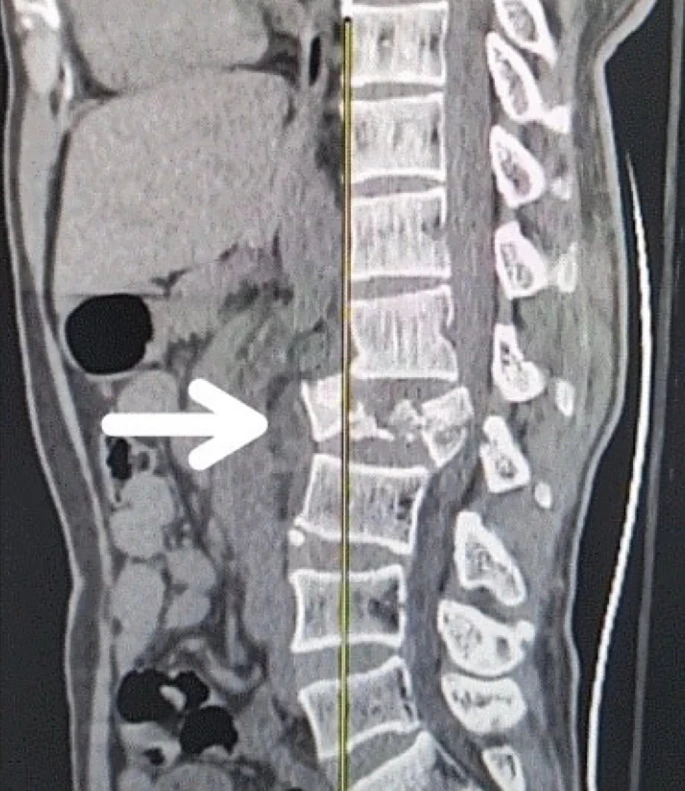

慢性期開(kāi)始于損傷后約3-6個(gè)月,并持續患者的余生,典型特征是囊腫形成和嚴重的神經(jīng)膠質(zhì)瘢痕(圖2)。

圖2:X射線(xiàn)圖像顯示慢性期脊髓損傷,通常以囊腫形成為特征,如白色箭頭所示